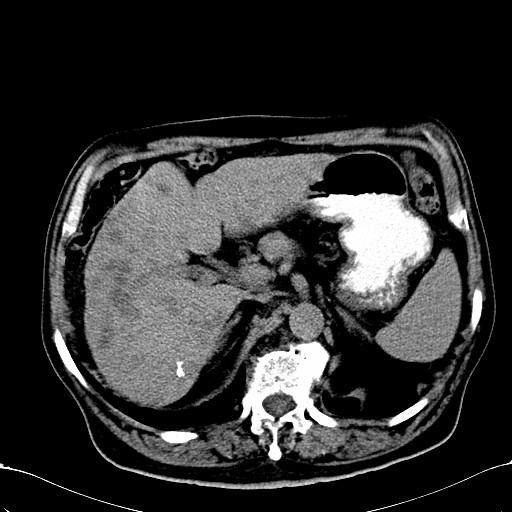

标题: CT28270:胰管扩张,肝多发占位 [打印本页]

标题: CT28270:胰管扩张,肝多发占位

患者,男,75岁。

考虑胰腺钩突癌并肝内转移,建议强化明确。

1)考虑胰头癌并肝脏多发性转移;建议行ct增强扫描检查。2)胃窦癌?建议行胃镜检查。

肝脏多方低密度结节,边缘模糊,考虑多发转移,胰管明显扩张,建议增强扫描钩突情况

肝脏多发低密度灶,胰头似呈低密度,胰管扩张,建议增强,

胰管显著扩张,但胆总管未见扩张征象,不太符合胰头占位!考虑慢性胰腺炎.胃窦占位并肝内转移可能!mrcp胃镜增强一起上!